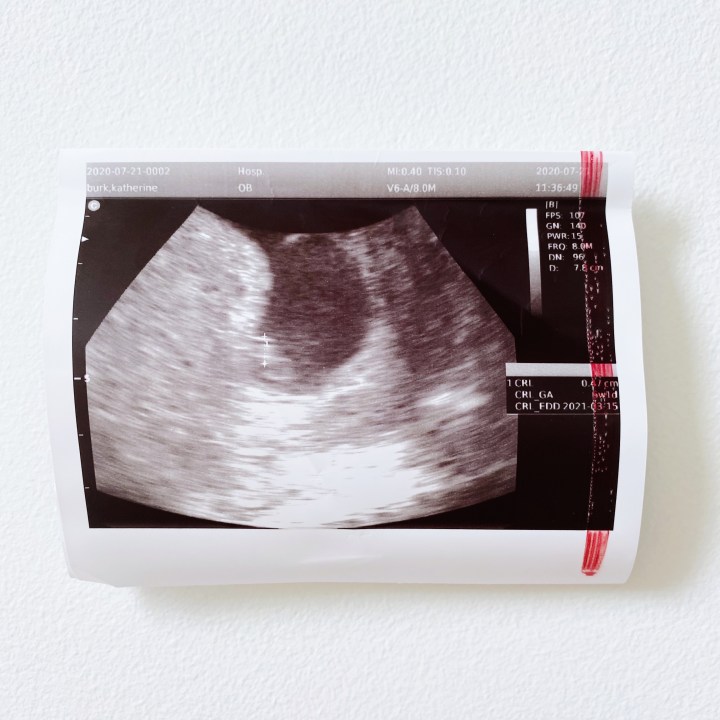

Things started to get really interesting around week eight. I went in for what we thought was my heartbeat appointment, but the baby was only measuring at 6 weeks. New due date: March 15, 2021.

Then, about a minute later, my doctor spotted a second sac. However, she only saw one baby. So, she sent me to a perinatal consultant to confirm whether or not I was pregnant with twins. Apparently/allegedly twins can measure small? That’s what I tried to tell myself, even though my mama gut instinct knew something was off. The term “vanishing twin” was also thrown out there.

The perinatal consultant only saw one baby, but the baby had what appeared to be a strong heartbeat. They decided to have me come back one week later to confirm whether I was pregnant with twins and to make sure things were progressing.

That brings us to Tuesday, July 28, 2020. I went to my appointment and I knew the second the nurse shook her head “no” to the doctor that something wasn’t right.

“No,” the perinatal specialist confirmed. “I’m sorry.”